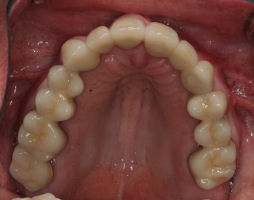

Before/After